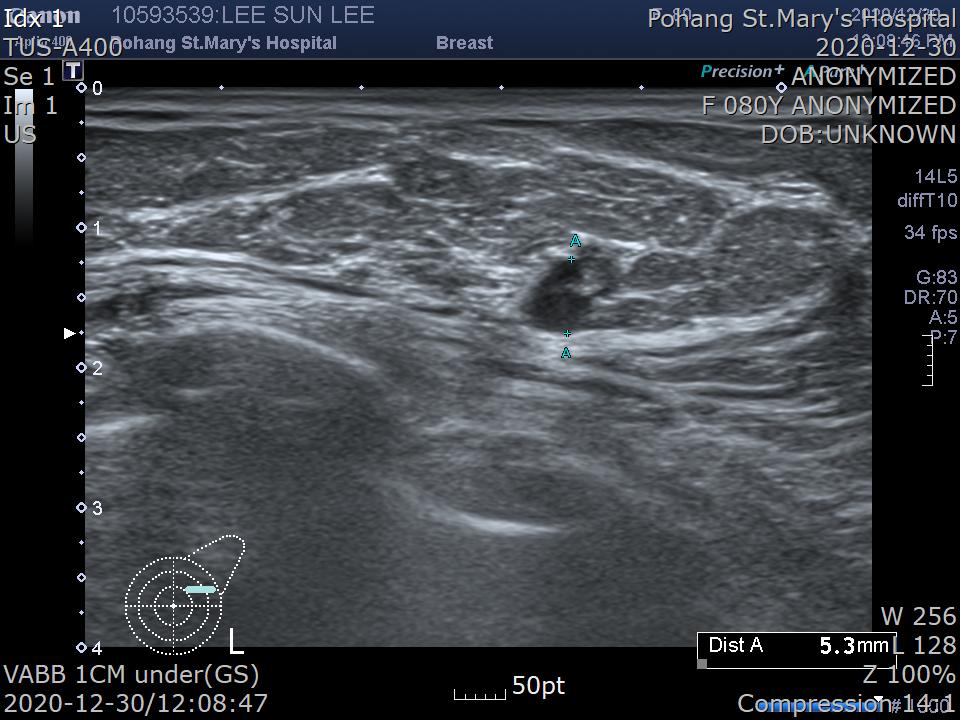

[유방 초음파]

Left : Conglomerated about 4~5mm sized round anechoic nodular images( 2:00~300, N-4cm ). ---> Cyst(C2), probably. R/O Fibroadenoma(Category 3).

왼쪽 유방에 2시~3시 방향, 유두에서 4cm 거리에 4~5mm s크기의 결절이 뭉쳐져(conglomerated) 있다는 소견이고 낭종 또는 섬유선종이 의심된다. Category 3 병변으로 확인된다는 소견입니다.

2020.12.30일 진공보조유방생검을 시행했습니다.

종양을 초음파로 먼저 확인합니다. 왼쪽 유방 상외측에 종양이 보이시죠?

결절(nodule)이 보이고 그 아래쪽으로 VABB probe가 보입니다.

한번 잘라내면 종양이 일부 절제됩니다. 여러번 반복하여 종양을 절제해 냅니다.